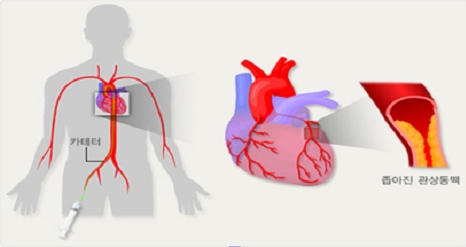

불안정 협심증 : 죽상 경화병변이 파열되어 혈전이 생겨서 급작스럽게 협착이 심해져서 생기는 경우를 말해요. 급작스럽게 협착이 심해지므로 예고 없이 증상이 나타날 수 있으며 관상동맥이 좁아져 심장으로 가는 혈류가 급속하게 떨어지므로 가슴 흉통의 증상이 나타날 수 있어요.

협심증 초기증상 세번째는 호흡 곤란인데요. 많은 사람들이 호흡에 문제가 생겨 힘들어 하는 경우가 있는데, 이는 협심증 초기증상으로 가슴 통증이 악화되어 호흡 곤란을 일으키기 때문인데요. 호흡 곤란은 일반적으로 운동, 격렬한 활동 또는 극심한 스트레스를 받을 때 발생해요. 관상동맥 협착이 아주 한 경우 혹은 급성 혈전증이 발생하게 되면 휴식 후에도 증상이 가라앉지 않고 호흡곤란이 지속될 수 있어요.